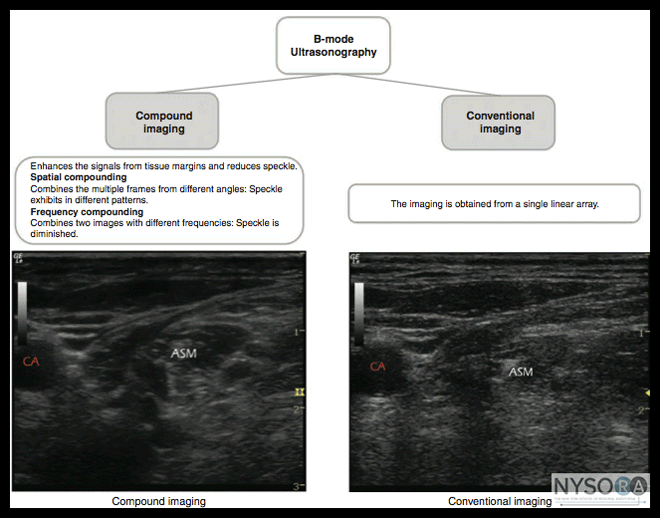

Author: Daquan Xu Optimizing an image produced by ultrasound is an essential skill for performance of an ultrasound-guided nerve block. Anatomically, peripheral nerves are often located in the vicinity of an artery or between muscle layers. The echo texture of normal peripheral nerves can have a hyperechoic, hypoechoic, or honeycomb pattern (Figure 1). Several scanning steps and techniques can be used to facilitate ade- quate nerve imaging, including the selection of sonographic modes, adjustment of function keys, needle visualization, and interpretation of image artifacts. All in all, sonographic imaging modes used for ultrasound- guided regional anesthesia and medical diagnostics are conventional imaging, compound imaging, and tissue harmonic imaging (THI). The conventional imaging is generated by a single-element angle beam. The compound imaging is implemented by acquiring several (usually three to nine) overlapping frames from different frequencies or from different angles. The tissue harmonic imaging acquires the information from harmonic frequencies generated by ultrasound beam transmission through tissue, which improves tissue contrast by suppression of scattering signals. Compound imaging with The tissue harmonic imaging can provide images with better resolution, penetration, and interfaces and margin enhancement, compared with those obtained using conventional sonography. In Figure 2, compound imaging and conventional imaging was used to view the interscalene brachial plexus. There is a clear margin definition of two hypoechoic oval-shaped nerve structures in compound imaging. As an example, the contrast resolution between the anterior scalene muscle and the surrounding adipose tissue is enhanced in comparison with those made with conventional imaging techniques. Five function keys on an ultrasound machine are of crucial importance to achieve an optimal image during the performance of peripheral nerve imaging (Figure 3A). 1. Depth: The depth of the nerve is the first consideration when ultrasound-guided nerve block is performed. The depth at which peripheral nerves are positioned and therefore imaged greatly varies and also depends on a patient's habitus. An optimal depth setting is important for proper focusing properties during imaging. Table 1 describes the recommended initial depth settings for common peripheral nerves. The target nerve should be at the center of the ultrasound image to obtain the best resolution of the nerve and reveal other anatomic structures in the vicinity of the nerve. For example, ultrasound imaging during supraclavicular or infraclavicular brachial plexus blockade requires that first rib and pleura are viewed simultaneously to decrease the risk of lung puncture with the needle.

Figure 2: Examples of image quality typically obtained with conventional versus compound imaging.